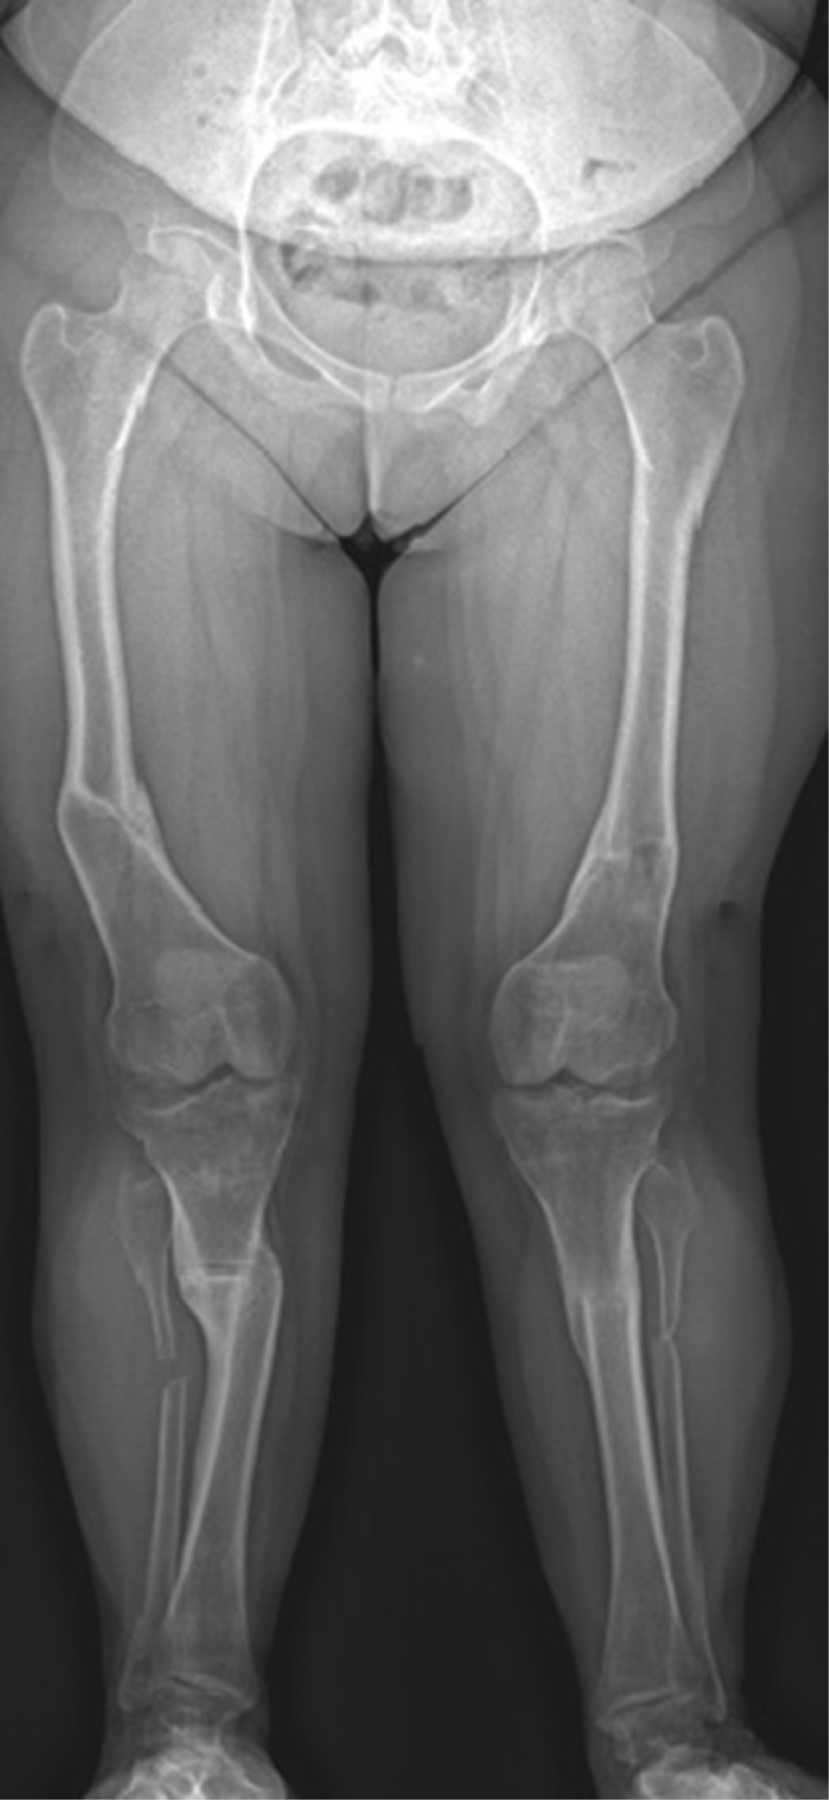

En esta paciente se decidió iniciar con crecimiento guiado por la edad. Intentando lograr la mayor corrección posible, tomando en cuenta lo poco predecible del crecimiento óseo en estos pacientes. Iniciamos con su primera cirugía a la edad de 10.4 años, siendo una hemiepifisiodesis tibial proximal medial bilateral y femoral distal medial bilateral con placas en 8 (Figura 5).

En la actualidad, con edad de 16 años, cuenta con mejoría a la marcha siendo claudicante, no dolorosa. Alineación de miembros pélvicos. Flexión de rodillas a 100 grados de manera bilateral. Con últimas mediciones radiográficas: MAD de 25 mm derecho y 25 mm izquierdo (Figura 7).

Figura 5

Figura 7